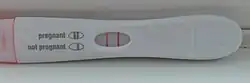

Pregnancy test

A pregnancy test is used to determine whether a woman is pregnant or not. The two primary methods are testing for the pregnancy hormone (human chorionic gonadotropin (hCG)) in blood or urine using a pregnancy test kit, and scanning with ultrasonography.[1] Testing blood for hCG results in the earliest detection of pregnancy.[2] Almost all pregnant women will have a positive urine pregnancy test one week after the first day of a missed menstrual period.[3]

Qualitative tests (yes/no or positive/negative results) look for the presence of the beta subunit of human chorionic gonadotropin in blood or urine. For a qualitative test the thresholds for a positive test are generally determined by an hCG cut-off where at least 95% of pregnant women would get a positive result on the day of their first missed period.[11] Qualitative urine pregnancy tests vary in sensitivity. High-sensitivity tests are more common and typically detect hCG levels between 20 and 50 milli-international units/mL (mIU/mL). Low-sensitivity tests detect hCG levels between 1500 and 2000 mIU/mL and have unique clinical applications, including confirmation of medication abortion success.[12] Qualitative urine tests available for home use are typically designed as lateral flow tests.